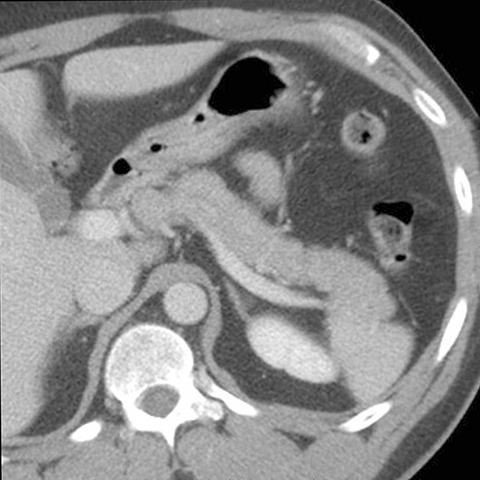

Normal spleen, axial view (CT) [2 of 5]